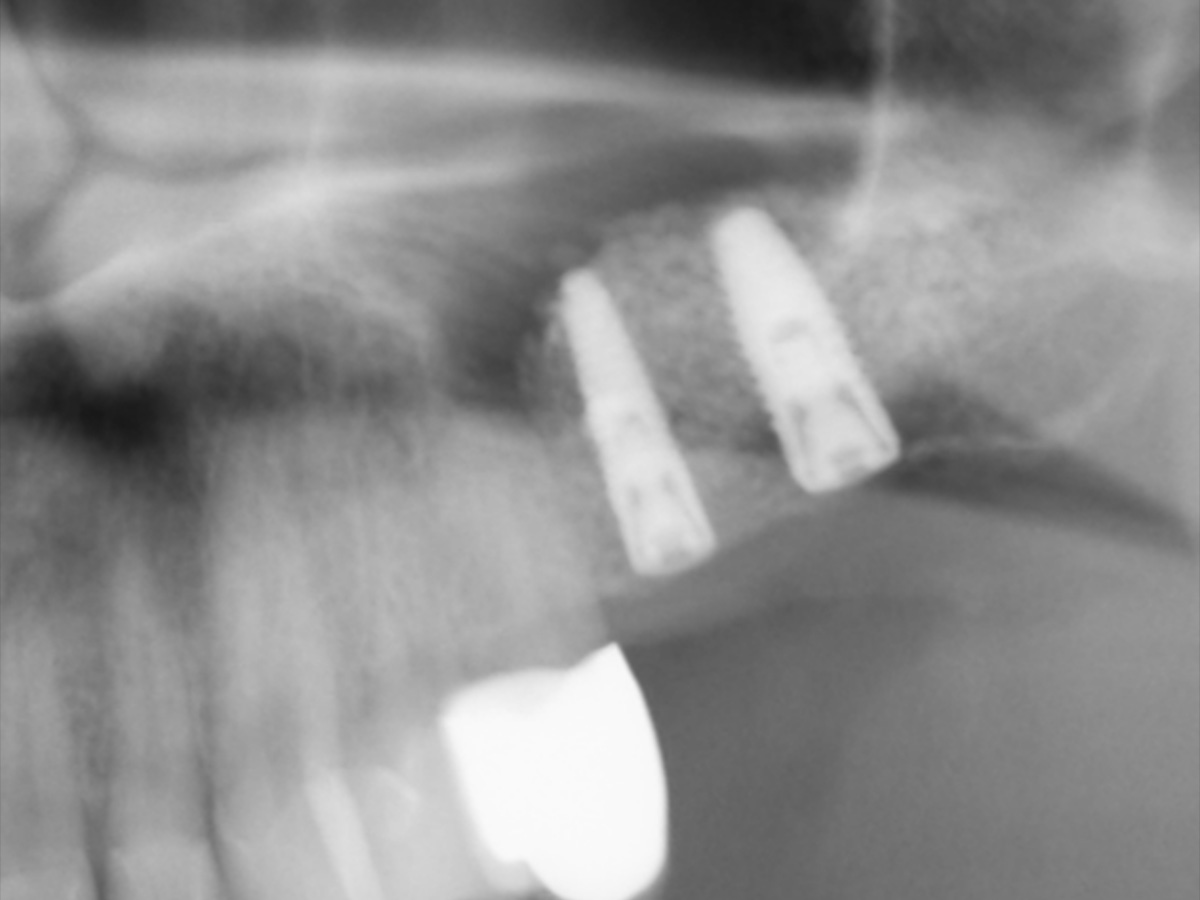

Abbildung 8

OPG nach Implantinsertion (Ausschitt).